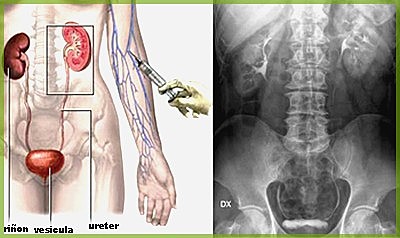

• Sistema Vascular

Sistema Vascular

Dr. Moses Swick, un urólogo estadounidense y Alexander Von Lichtenberg en Berlín, probó el uroselectan. Este fue un avance importante en la investigación del sistema vascular, y permitió la realización de la pielografía intravenosa.